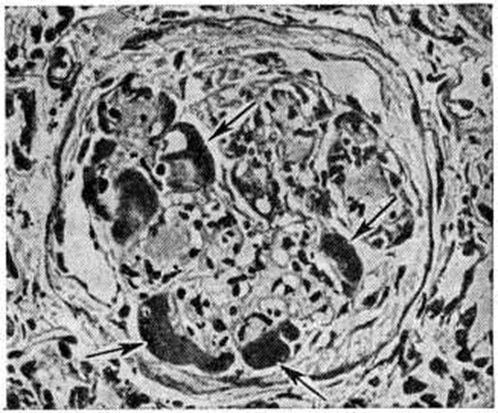

Экссудативная форма встречается реже, чем предыдущие, и характеризуется прежде всего так называемый «фибриноидными шапочками», которые представляют собой отложения PAS-положительного материала между эндотелием и базальной мембраной капилляров (рисунок 4). При иммуногистохимическом исследовании в этих образованиях обнаруживается значительное количество комплементсвязывающих иммуноглобулинов, что даёт основание считать их комплексом антиген—антитело, а не сывороточным экссудатом. «Фибриноидные шапочки» не являются специфическими для Гломерулосклероз диабетический, но вместе с тем они обнаруживаются при тяжёлых и быстро прогрессирующих его формах. С ними часто сочетаются так называемый «капсульные капли», располагающиеся на внутренней стороне боуменовой капсулы.

Рис. 4.

Микропрепарат почки при экссудативной форме гломерулосклероза: клубочек с хорошо выраженными «фибриноидными шапочками» (указаны стрелками); окраска гематоксилин-эозином; ×400.